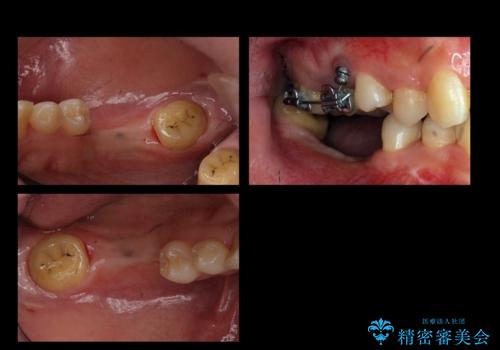

- 奥歯が虫歯で他院で抜かないといけないといわれ来院。

虫歯を放置していたが、これを機にしっかり通って治したいとのことでした。

右下は虫歯がひどく、抜歯が必要でした。また、右下の一番奥の歯は親知らずのため使うことができない状態でした。